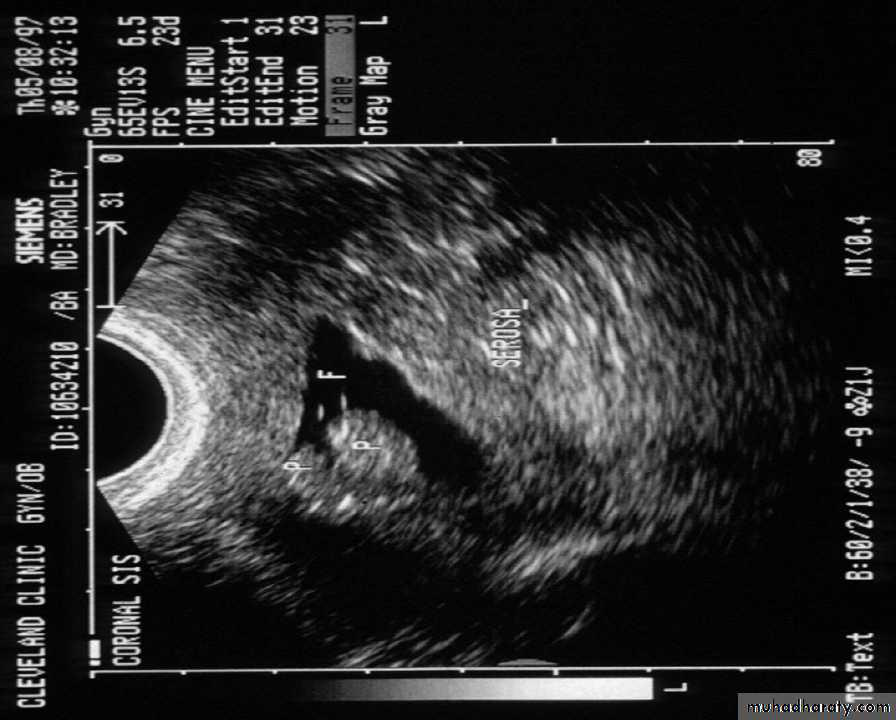

A refinement of vaginal probe ultrasound is saline infusion sonography (SIS). A salt water (saline) solution is injected into the uterus with a small tube (catheter) before the vaginal probe is inserted. The presence of liquid in the uterus helps make any structural abnormalities more distinct. These two non-invasive procedures cause less discomfort than endometrial biopsies and D & Cs, but D & C still remains the definitive test for diagnosing uterine cancer.